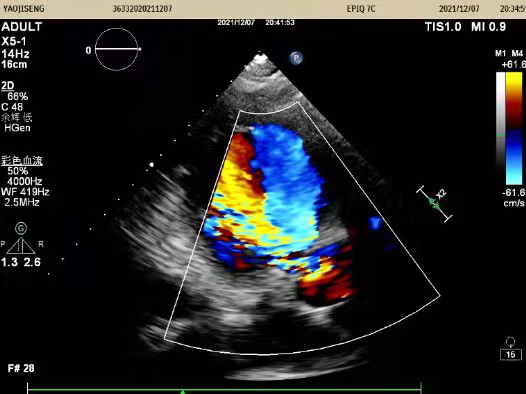

术前心脏超声:

提示